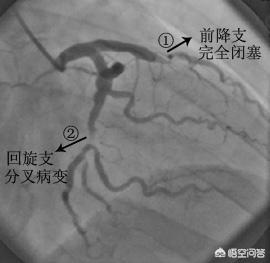

- Les produits de contraste "éclairent" les artères coronaires :Les artères coronaires du corps humain sont relativement petites : le tronc principal des artères coronaires ne mesure que cinq ou six millimètres, certaines des branches les plus importantes mesurent environ deux ou trois millimètres, et les autres sont des branches encore plus petites ; ces vaisseaux sanguins sont reliés aux tissus environnants et sont recouverts par les os, les muscles, etc. devant eux. Lors de la coronarographie, un agent de contraste est injecté à l'intérieur du cathéter mentionné plus haut afin de remplir les artères coronaires d'agent de contraste.L'agent de contraste est un médicament imperméable aux rayons X qui "illumine" les artères coronaires pendant la coronarographie afin que nous puissions voir clairement la distribution, la taille et la présence de sténoses et d'obstructions dans les artères coronaires.

- La DSA (Digital Subtraction Angiography) est une caméra pour les vaisseaux sanguins :L'équipement utilisé pour prendre des photos des artères coronaires mentionné plus haut est le DSA, qui est en fait également une forme d'examen aux rayons X, capable de prendre des photos et d'enregistrer des vidéos des différentes artères coronaires sous de multiples angles tout en injectant le produit de contraste, ce qui peut être considéré comme un angle de 360 degrés sans issue, et ces photos et vidéos peuvent être déposées sur un CD-ROM pour être facilement conservées et analysées.C'est parce que la coronarographie permet d'obtenir des photographies et des vidéos d'une telle clarté que la coronarographie est l'étalon-or du diagnostic de la maladie coronarienne.